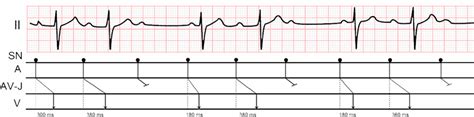

AV Block Second-Degree Wenckebach, also known as Mobitz type I second-degree AV block, is a heart condition characterized by a progressive prolongation of the PR interval on an electrocardiogram (ECG) until a beat is dropped. Before we get too deep, let’s break that down a bit. Your heart’s electrical system controls how it beats. The signal starts in the sinoatrial (SA) node, travels to the atrioventricular (AV) node, and then down to the ventricles. This coordinated sequence ensures that your heart pumps blood effectively. In a healthy heart, the electrical signal moves smoothly from the atria (the upper chambers) to the ventricles (the lower chambers) through the AV node. The PR interval represents the time it takes for the electrical impulse to travel from the atria to the ventricles. In Wenckebach, this interval gradually increases with each beat until one beat is completely blocked, and the ventricles don’t contract. After the blocked beat, the cycle repeats itself. So, you’ll see a pattern of increasing PR intervals followed by a dropped beat on an ECG. This pattern is typically regular, making it somewhat predictable. AV Block Second-Degree Wenckebach is usually benign and often doesn’t cause noticeable symptoms. However, it’s essential to understand the condition, its causes, and potential complications. Recognizing this pattern on an ECG is crucial for diagnosis, and appropriate management can prevent more severe heart issues. Wenckebach block is more common than Mobitz Type II second-degree AV block and is usually found at the AV node level. The progressive prolongation of the PR interval before the dropped beat is what really sets Wenckebach apart.

When it comes to AV Block Second-Degree Wenckebach, symptoms can be subtle, or even nonexistent, making diagnosis tricky. AV Block Second-Degree Wenckebach might not always present obvious symptoms, especially if the heart block is mild or intermittent. In many cases, individuals with this condition may not experience any noticeable signs, and the heart block is only discovered during a routine electrocardiogram (ECG) or other cardiac testing. However, when symptoms do occur, they can vary in intensity and nature. Some people may feel lightheaded or dizzy, particularly if the heart block causes a significant drop in heart rate. This can happen because the ventricles aren’t contracting as often as they should, reducing blood flow to the brain. Another common symptom is fatigue, which can result from the heart not pumping blood efficiently enough to meet the body’s needs. Individuals might find themselves feeling unusually tired or weak, even after minimal physical exertion. In more severe cases, some people may experience syncope, or fainting spells. This occurs when the heart block leads to a prolonged pause in heartbeats, causing a temporary loss of consciousness due to insufficient blood flow to the brain. Palpitations, or the sensation of skipped heartbeats, can also be a symptom. This happens because of the irregular heart rhythm caused by the dropped beats characteristic of Wenckebach block. Shortness of breath can occur if the heart’s ability to pump blood is significantly impaired, leading to fluid buildup in the lungs. Diagnosing AV Block Second-Degree Wenckebach typically involves an ECG, which records the electrical activity of the heart. The classic Wenckebach pattern, characterized by a progressive prolongation of the PR interval followed by a dropped beat, is usually evident on the ECG tracing. Sometimes, the heart block may not be present during a standard ECG, particularly if it’s intermittent. In such cases, a Holter monitor, which records the heart’s electrical activity over 24 to 48 hours, may be used to capture the heart block. An exercise stress test, where the heart’s activity is monitored during physical exertion, can also help reveal the heart block. An electrophysiology (EP) study, an invasive procedure where catheters are inserted into the heart to assess its electrical properties, may be performed in complex cases to pinpoint the location and severity of the block.